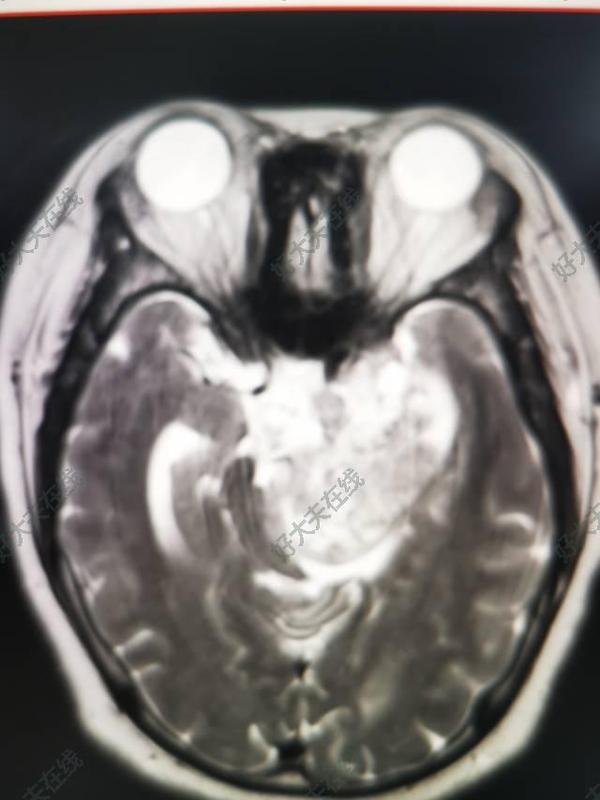

腦室內(nèi)腫瘤內(nèi)窺鏡微創(chuàng)手術(shù)的策略

腦室內(nèi)占位病變,尤其是腫瘤,在出現(xiàn)癥狀時病變往往已經(jīng)侵襲重要的神經(jīng)傳導(dǎo)束、神經(jīng)核,或者梗阻了腦脊液循環(huán)的途徑,多數(shù)已經(jīng)進(jìn)展到了腫瘤的后期。早期發(fā)現(xiàn)腦室內(nèi)腫瘤或者占位病變,早期實施腦室內(nèi)占位性病變的微創(chuàng)手術(shù),可以避免腫瘤組織對腦室壁重要結(jié)構(gòu)的侵襲,甚至可以實現(xiàn)早期對腫瘤進(jìn)行根治性手術(shù)。腦室內(nèi)占位在早期的病程中,往往因為腦室沒有擴大,癥狀極為隱襲不典型,多數(shù)是偶然其他原因查體而發(fā)現(xiàn)。初期往往腦室狹小,狹小的腦室對微創(chuàng)手術(shù)器械和設(shè)備的進(jìn)入造成極大的限制。所以,選擇合理的手術(shù)入路對于降低手術(shù)創(chuàng)傷,并能夠完成早期切除腫瘤,至關(guān)重要。我們醫(yī)療團隊結(jié)合核磁共振神經(jīng)纖維束的頭投射、以及立體定向和術(shù)中超聲探測的應(yīng)用,①選擇最合適并有效的避免腦實質(zhì)的損傷的手術(shù)通路,②盡量滿足美容要求的體表切口,③利用我們特制的微創(chuàng)手術(shù)器械,避免器械擺動對腦實質(zhì)的騷擾或挫傷,對腫瘤進(jìn)行根治性切除,達(dá)到了良好的效果。病例分享:青年女性,查體發(fā)現(xiàn)右側(cè)腦室內(nèi)腫物,間隔9月復(fù)查腫物增大,影像診斷室管膜下瘤,主觀意愿切除,為防腫瘤逐步侵入腦實質(zhì)選擇手術(shù),因腫瘤位于腦室體部,開顱手術(shù)切除損失較大毗鄰運動區(qū),本人忌諱開顱;內(nèi)窺鏡手術(shù),腦室不大,腦室鏡勉強進(jìn)入,發(fā)際切口鉆孔,進(jìn)入腦室與腦室體部成角,原公司配套工具不能分離切除腫瘤周邊,本團隊采用自制可變曲度消融電極,在不擺動腦室工作鞘情況下逐步切除腫瘤?;颊咝g(shù)后清醒四肢遵囑活動。